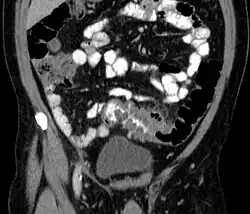

Diverticulitis on a CT scan in a coronal view

People with the above symptoms are commonly studied with computed tomography, or a CT scan.[37] Ultrasound can provide preliminary investigation for diverticulitis. Amongst the findings that can be seen on ultrasound is a non-compressing outpouching of bowel wall, hypoechoic and thickened wall, or an obstructive fecalith at the bowel wall. Besides, bowel wall oedema with adjacent hyperechoic mesentery can also be seen on ultrasound. However, a CT scan is the mainstay of diagnosing diverticulitis and its complications.[12] The diagnosis of acute diverticulitis is made confidently when the involved segment contains diverticula.[38] CT images reveal localized colon wall thickening, with inflammation extending into the fat surrounding the colon.[39] Amongst the complications that can be seen on CT scan are: abscesses, perforation, pylephlebitis, intestinal obstruction, bleeding, and fistula.[12]